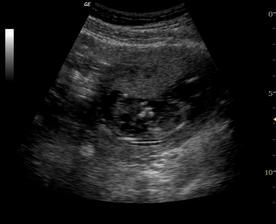

♥ dne 12.8.2008 čeká nás větší KO u gynekologa - vše v pořádku, mrňousek se nám krásně předvedl, pil plodovou vodu a pěkně si u toho pomlaskával (v tom vedru nebylo divu 😉 ), dupal jak zajíček 🙂..., byl úúúúúúžasný a má už 300g. Mamina se také pěkně zakulacuje - má už 62,9 kg tj. 7 kg nahoře

♥ dne 20.8.2008 2. screening ve 20tt - brouček se sice schovával do placenty, ukazovat se moc nechtěl, ale závěr je: čekáme zdravého chlapečka nebo zdravou holčičku..., prostě čekáme zdravé MIMINKO 🙂 které nyní váží 350g